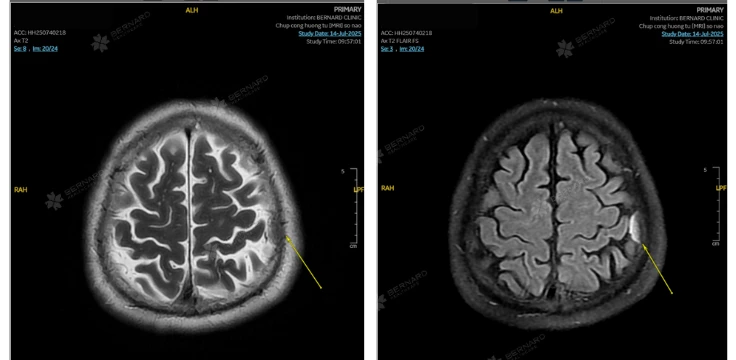

Trong lĩnh vực chẩn đoán hình ảnh hiện đại, chụp cộng hưởng từ (MRI) sọ não được xem là kỹ thuật tiên tiến nhất trong khảo sát não bộ. Với khả năng hiển thị chi tiết cấu trúc mô mềm, mạch máu và các biến đổi vi thể, MRI không chỉ giúp phát hiện sớm các tổn thương mà còn đóng vai trò quan trọng trong việc lập kế hoạch điều trị và theo dõi tiến triển bệnh lý thần kinh.

MRI sọ não cho phép dựng ảnh đa mặt phẳng (axial, sagittal, coronal) và tái tạo hình ảnh ba chiều, giúp quan sát rõ ràng từng cấu trúc như tiểu não, thân não, các thùy vỏ não, xoang tĩnh mạch, mạch máu não, tuyến yên, dây thần kinh sọ… Độ tương phản cao giữa các mô giúp phát hiện những tổn thương chỉ vài milimet – điều mà CT thường không cho thấy.

So với CT Scan hay các phương pháp truyền thống, MRI cho phép tái hiện hình ảnh với độ phân giải cao, phát hiện tổn thương nhỏ ở kích thước chỉ vài milimet. Đây là công cụ quan trọng giúp bác sĩ đánh giá toàn diện tình trạng não và mạch máu não, bao gồm:

Ở người trung niên có tiền sử tăng huyết áp, rối loạn lipid máu, đái tháo đường hoặc stress kéo dài, MRI có thể phát hiện vi tổn thương mạch máu nhỏ (microvascular disease) - dấu hiệu sớm của thoái hóa thần kinh và suy giảm trí nhớ.